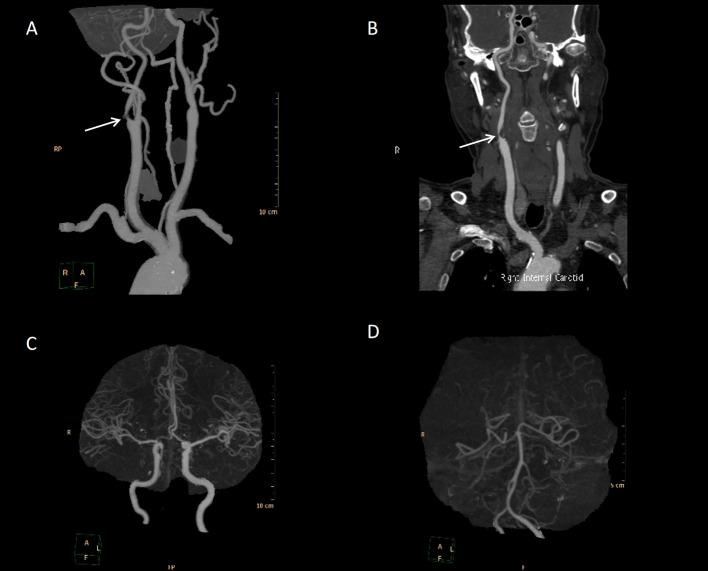

Severe headache as the initial clinical manifestation of early neurological deterioration (END) is uncommon. The emergence of severe headache should be promptly recognized as a potential indicator of large vessel stenosis. Here, we describe a male patient who initially presented with severe headache accompanied by transient left limb weakness, which subsequently progressed to persistent weakness. Imaging studies revealed severe stenosis at the origin of the right internal carotid artery, along with the presence of asymmetrically prominent cortical veins (APCV). Despite the administration of pregabalin orally and tramadol intramuscularly, his headache persisted. However, significant alleviation of his headache symptoms was observed following the improvement of cerebral perfusion. Re-examination revealed the resolution of cortical vein dilation. This case underscores the importance of recognizing severe headache and APCV as potential indicators of large vessel stenosis and early neurological deterioration (END). Improving cerebral perfusion may serve as an effective means of alleviating headache symptoms in such cases.

严重头痛作为早期神经功能恶化(END)的初始临床表现并不常见。严重头痛的出现应迅速被识别为大血管狭窄的潜在指标。在此,我们描述一名男性患者,其最初表现为严重头痛并伴有短暂性左下肢无力,随后进展为持续性无力。影像学研究显示右颈内动脉起始处严重狭窄,同时存在不对称突出的皮质静脉(APCV)。尽管口服了普瑞巴林并肌肉注射了曲马多,他的头痛仍持续存在。然而,随着脑灌注的改善,观察到他的头痛症状明显缓解。复查显示皮质静脉扩张消失。该病例强调了将严重头痛和APCV识别为大血管狭窄和早期神经功能恶化(END)潜在指标的重要性。改善脑灌注可能是缓解此类病例头痛症状的有效手段。